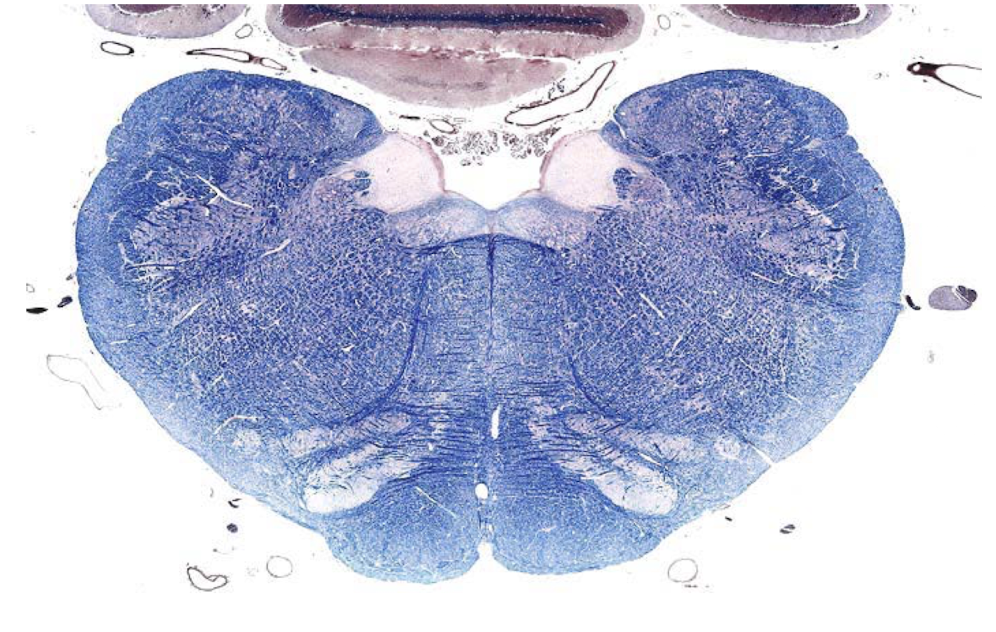

what section of the brain is shown?

caudal medulla

- open 4th ventricle

- olivary nucleus

- pyramids (indicate medulla)